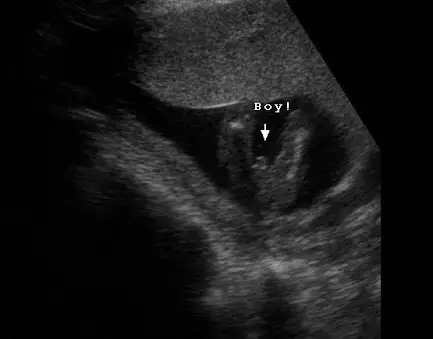

kızlarr :) 12+3 günlüğüz doktor kız dedi :) tahminler tuttu yani :) tekrar bi bakın :)

kızlar 12 haftalık...

doktor birdahakı ay bakalım yanılma çok oluyor dedi....sizce ?

ben başından beri erkek hissediyorum ama yanılabılırım